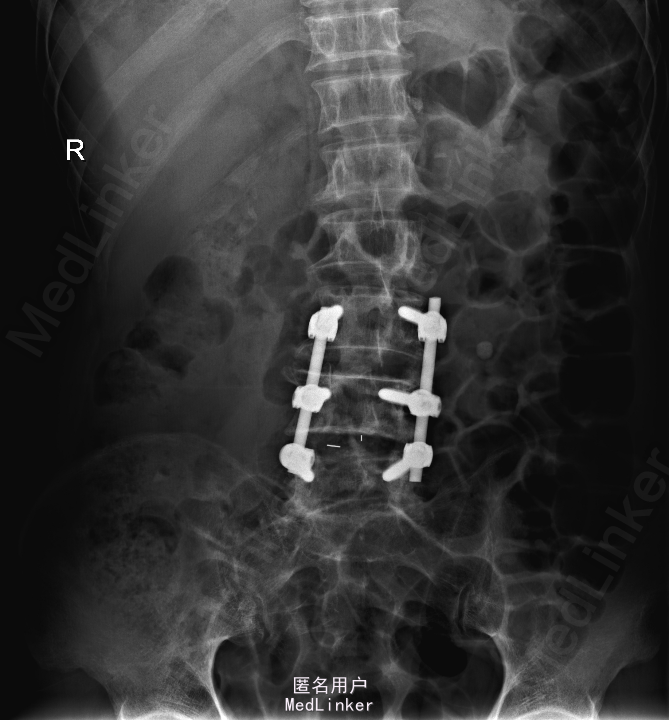

诊断:腰椎椎管狭窄 处理: 1、完善相关辅助检查,明确诊断,有无手术指证; 2、完善手术评估,有无手术禁忌,手术风险及并发症; 3、在全麻下行腰椎后路减压,腰3/4左侧椎板减压,腰4/5椎间Cage植骨融合内固定术

随访 术后患者下肢麻木感觉较前好转,左侧踝背伸、跖屈肌力4级+,左侧肢体抬高试验阴性。术后MR检查减压彻底 讨论:1、腰椎椎管狭窄手术指证的把握,腰椎后路手术,腰椎椎间融合与椎板减压的选择? 2、术中探查如无明显间盘突出,以椎管骨性狭窄为主,可行腰椎后路椎板减压为主。